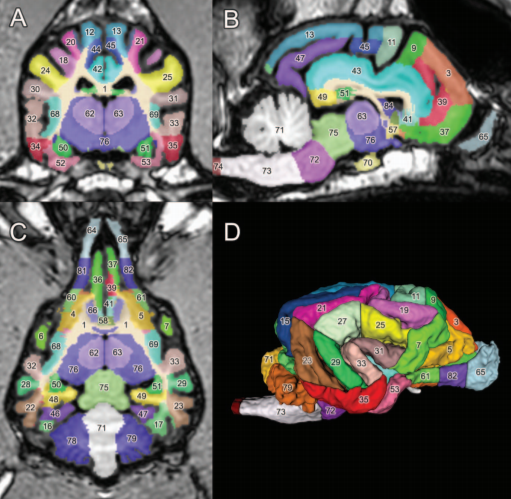

A detailed canine brain label map for neuroimaging analysis

Dogs have recently become an important model species for comparative social and cognitive neuroscience. Brain template-related label maps are essential for functional magnetic resonance imaging (fMRI) data analysis, to localize neural responses. In this study, we present a detailed, individual-based, T1-weighted MRI-based brain label map used in dog neuroimaging analysis. Methods: A typical, medium-headed dog (a 7.5-year-old male Golden Retriever) was selected from a cohort of 22 dogs, based on brain morphology (shape, size, and gyral pattern), to serve as the template for a label map. Results: Eighty-six 3-dimensional labels were created to highlight the main cortical (cerebral gyri on the lateral and medial side) and subcortical (thalamus, caudate nucleus, amygdala, and hippocampus) structures of the prosencephalon and diencephalon, and further main parts of brainstem (mesencephalon and rhombencephalon). Discussion: Importantly, this label map is (a) considerably more detailed than any available dog brain template; (b) it is easy to use with freeware and commercial neuroimaging software for MRI and fMRI analysis; and (c) it can be registered to other existing templates, including a recent average-based dog brain template. Using the coordinate system and label map proposed here can enhance precision and standard localization during future canine neuroimaging studies.